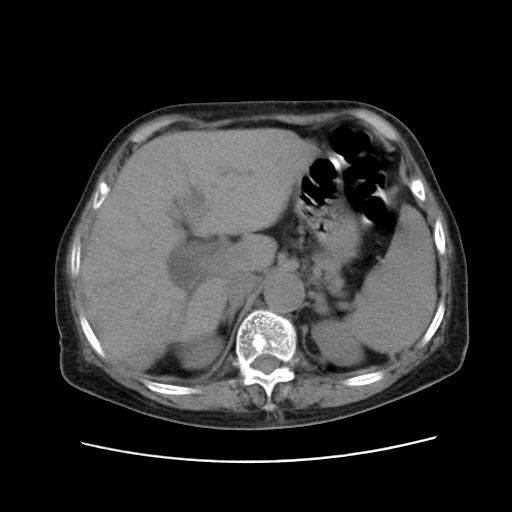

女,77.无不适

肝旁多发胆囊状液体影考虑肠腔积液基中部分囊状景不多外胆囊

肠子那块乱乱的没整明白

肝内胆管扩张,胆囊炎,胆囊窝积液。 右侧胸腔少量积液。

右侧肝内胆管局限性扩张,其内密度不均匀,扩张的胆管壁增厚,考虑肝内胆管炎合并结石可能性大